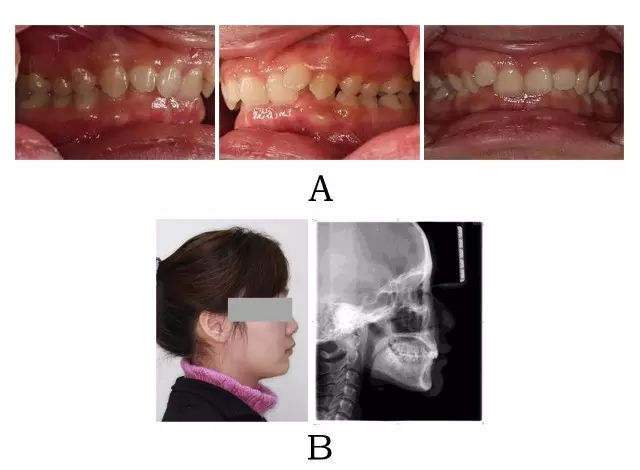

圖 4-9:嚴(yán)重混合 II 型突面畸形正頜正畸聯(lián)合治療結(jié)束后臨床療效及頭顱側(cè)位影像變化。

(A) 咬合改善 (B) 側(cè)貌改變

Figure 4-9. Treatment outcomes from ortho-orthognathic conjunction for merged prognathism (Type II). (A) Occlusion correction. (B) Facial esthetic improvement.

(2) 骨性嚴(yán)重、上頜牙內(nèi)傾性代償嚴(yán)重且已生長(zhǎng)發(fā)育完全停止的成人,可考慮用正頜正畸聯(lián)合治療。術(shù)前治療的要點(diǎn)是上前牙有限度的直立性去代償及下頜 Spee曲線的整平。由于下頜自動(dòng)前移釋放的潛力有限,在上前牙去代償后往往創(chuàng)造足夠的覆蓋,通常不需要通過拔中段牙創(chuàng)造覆蓋。術(shù)式通常是雙頜(上頜 LeFort I +下頜 BSSRO),由于頦部形態(tài)較好,一般不需要附加頦成形術(shù)[10](圖 4-7;4-8;4-9)。